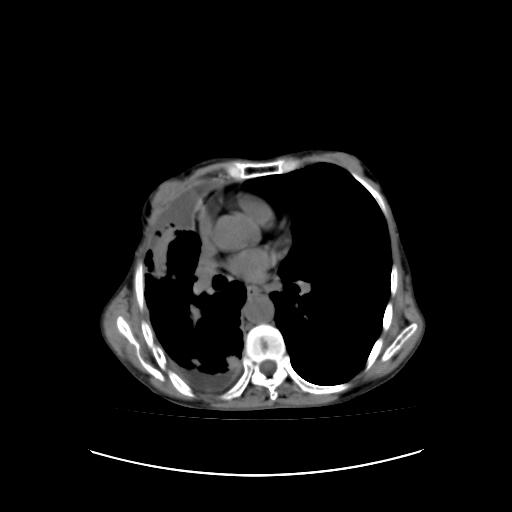

标题: CT16930:女 59 胸痛6个月 胸水脱落细胞学见瘤细胞 [打印本页]

标题: CT16930:女 59 胸痛6个月 胸水脱落细胞学见瘤细胞

可见多发肺内病灶,且胸膜病灶较多有圆球状而非丘状,多考虑胸膜转移瘤伴胸腔积液,右侧胸廓缩小固定,且部分病灶呈丘状,尚不除外恶性胸膜间皮瘤伴肺内转移

符合:恶性胸水的表现。多考虑恶性胸膜间皮瘤。

右侧胸廓塌陷,右侧胸膜广泛增厚并见多发胸膜结节,右侧少量胸腔积液并包裹。

右侧胸膜转移瘤,原发灶可能就在在右肺,另外建议检查右侧乳腺.